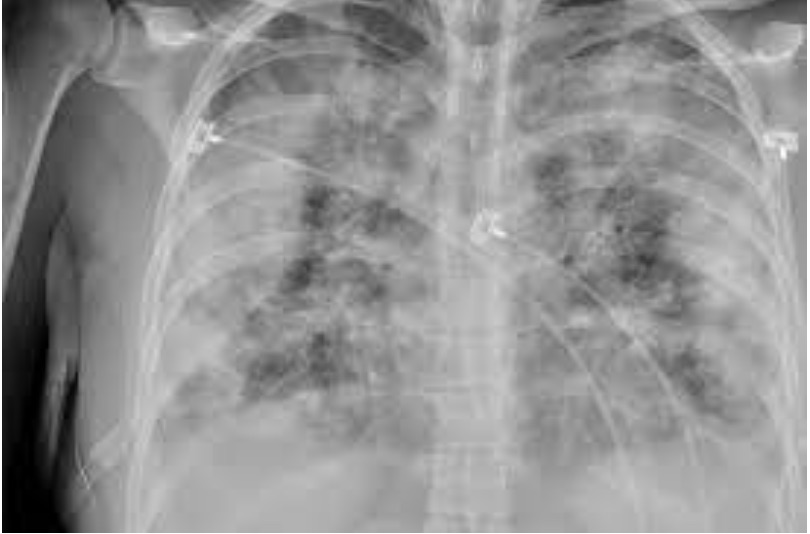

Acinetobacter baumannii (AB) est un pathogène difficile à traiter à l'origine de pneumonies sous respirateurs. Il peut être résistant à des degrés divers à toute une série d'antibiotiques comme l'imipénème, la ticarcilline, la gentamicine, la ciprofloxacine, la pipéracilline/tazobactam etc. mais reste sensible à la colistine et la rifampicine. Dans la liste OMS des bactéries contre lesquelles il est urgent de disposer de nouveaux antibiotiques, AB résistant aux carbapénèmes est en priorité 1 en compagnies de P. aeruginosa et des entérobacteriaceae résistants aux carbapénèmes. La mortalité associée varie de 28% à 84% selon les publications. Dans ce contexte, l'emploi de la colistine nébulisée (NC) est discuté sur base d'études antérieures aux résultats contradictoires notamment sur la réduction de la mortalité. Elle est utilisée à des doses quotidiennes plus élevées qu'auparavant alors qu'il y a peu de chance que ces doses améliorent le pronostic à une époque où le pourcentage de souches de AB résistantes à la colistine a tendance à augmenter.